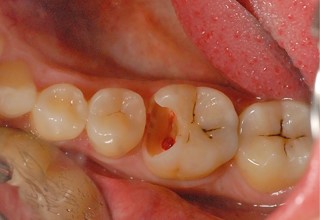

Large cavities and spreading pain

Untreated cavities can extend to the pulp, leading to severe pain and infection. If a visible hole in the tooth is accompanied by pain when chewing or consuming food, a root canal may be necessary.